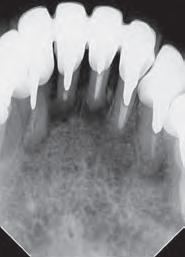

Dientes 31 y 41 - Reabsorción Interna / Conducto obturado con BIO-C® REPAIR. Imágenes cedidas por la Dra. Cimara Barroso.